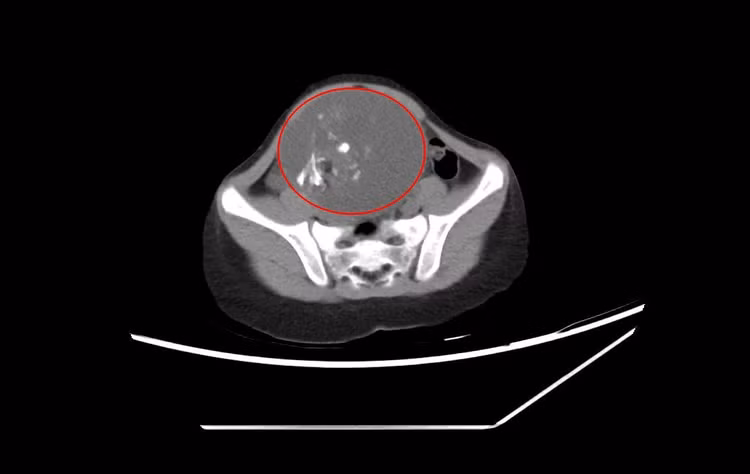

Qua siêu âm và chụp cắt lớp vi tính, bác sĩ phát hiện khối u kích thước vùng hạ vị kích thước lớn, ít di động, ấn gây đau tức. Bệnh nhi được chẩn đoán u buồng trứng và chỉ định phẫu thuật cắt u.

u-quai-buong-trung-6-tuoi-1.jpg

Hình ảnh chụp cắt lớp khối u buồng trứng kích thước lớn của bé gái 6 tuổi - Ảnh BVCC

Kíp mổ khoa Ngoại phối hợp với khoa Gây mê hồi sức thực hiện phẫu thuật. Qua đường rạch nhỏ ổ bụng, phẫu thuật viên khéo léo bóc tách khối u buồng trứng phải kích thước 10 cm, đồng thời cầm máu. Sau hơn 1 giờ, ca mổ diễn ra thuận lợi. Khối u buồng trứng phải đã được bóc tách, cắt bỏ trọn vẹn và đưa ra ngoài.